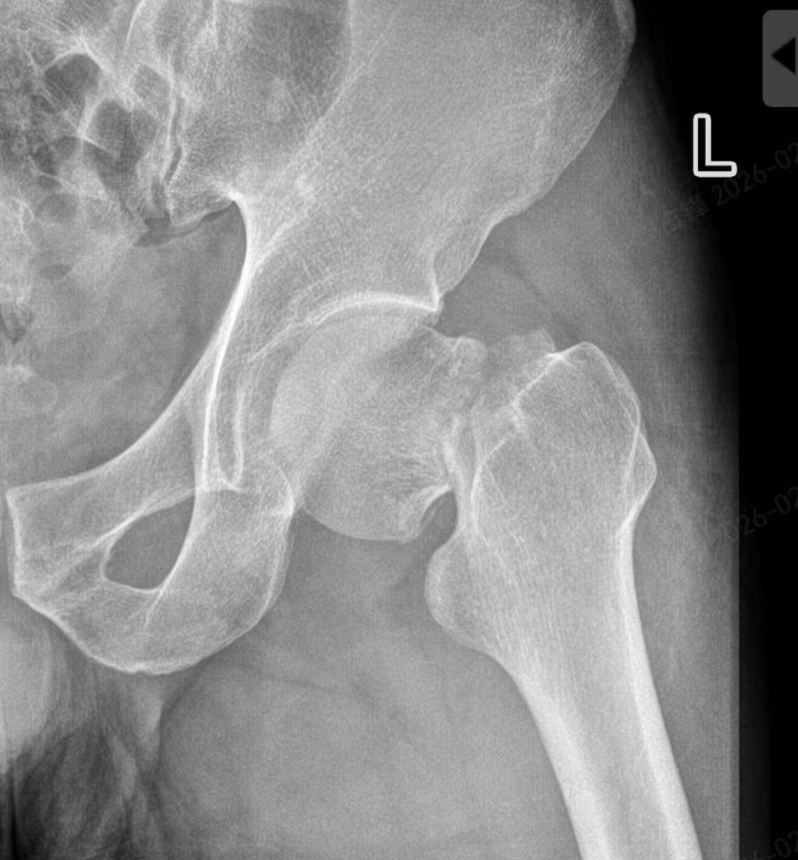

大年三十,王先生在浙江意外摔倒,左侧髋部剧痛难忍,被紧急送往当地医院,确诊为左侧股骨颈骨折。

接诊的骨科团队第一时间为他完善了影像学检查,明确了骨折分型和手术指征。

“股骨颈骨折的黄金手术时间窗很短,我们必须争分夺秒。” 作为主刀医生,高新院区创伤骨科周占锋迅速组织团队进行术前讨论,完善术前检查、协调器械、完成麻醉准备、制定精准的手术方案……